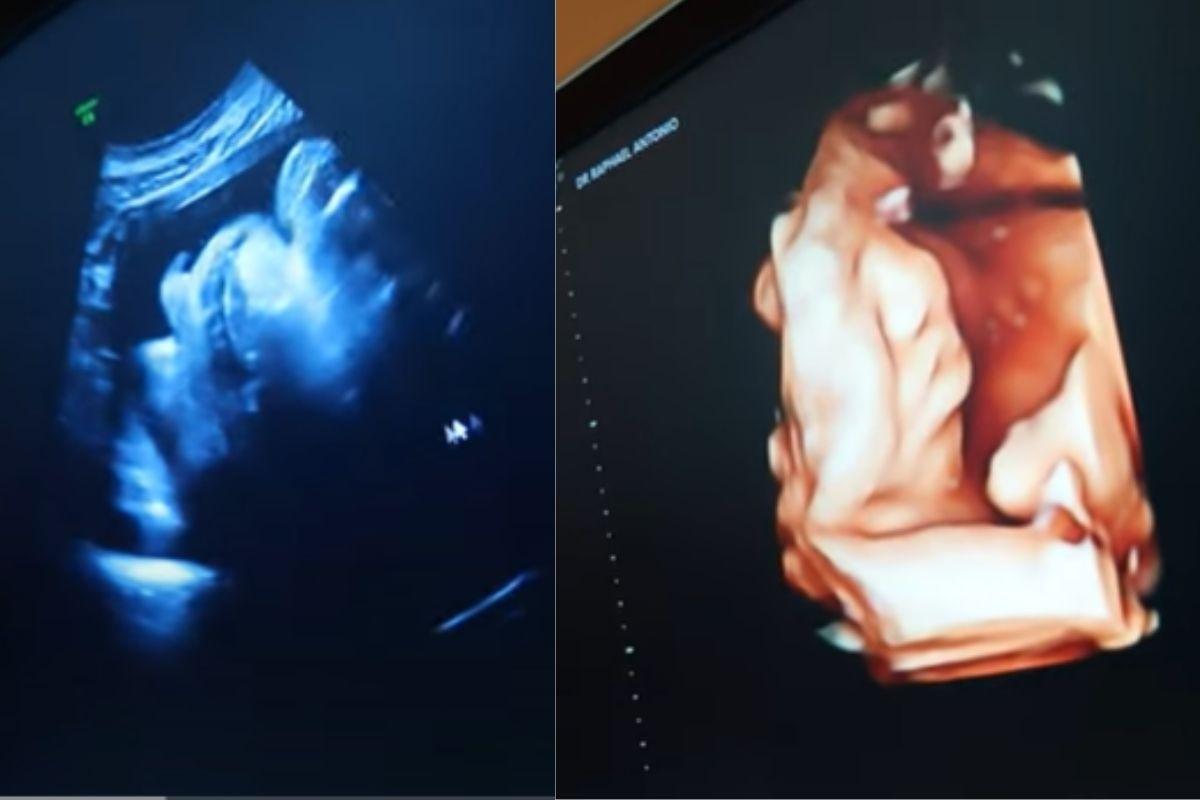

Entretanto, o médico começa a mostrar o nariz, a boca e a bochecha de Maria Alice. Logo depois, ele mostra o exame em 3D e é possível ver a bebê sorrindo e Virginia comemora. “É isso, agora Maria Alice pode chegar a qualquer momento”, diz a mãe já em casa ao lado de Zé Felipe.